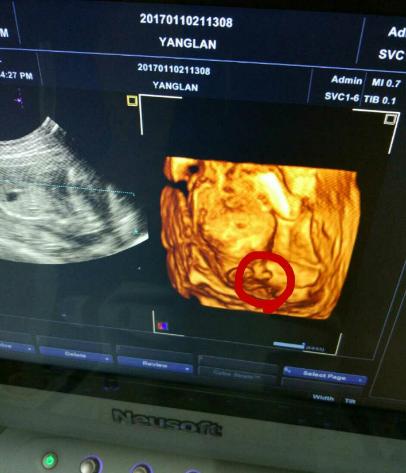

朋友怀孕几个月了,每隔一段时间就去检查。迫切地想知道肚子里是个“小鸡妞”,还是“小鸡仔”。前两天又去医院做了唐氏筛查,医院刚好新进了四维机,说是能看到辨别宝宝的性别,朋友兴奋的不得了,于是赶快做了一个检查。第一次看到宝宝动,好激动,医生很仔细的帮看,老公也在看,医生看大腿小鸡鸡好明显,我老公说小鸡鸡耶,医生说看到没有凸起来的那个就是小鸡鸡,朋友说:“听到自己肚子里是个小鸡仔的时候,眼泪不自觉地流了下来。”